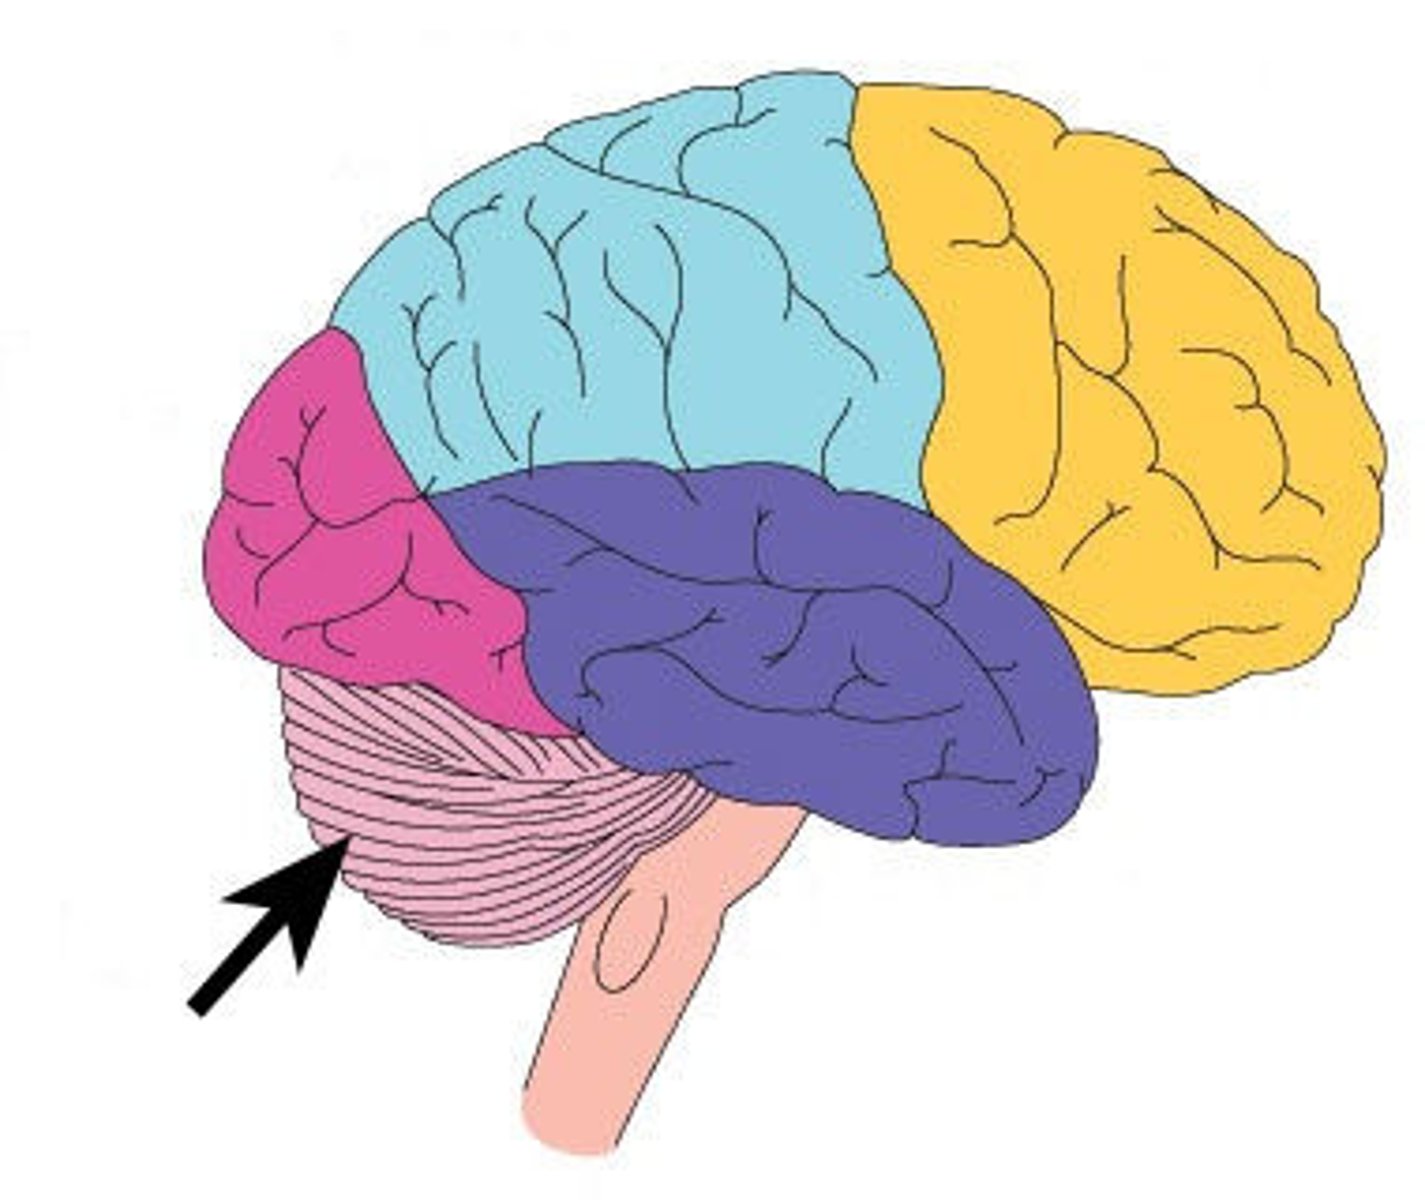

lobes of the cerebrum

frontal, parietal, temporal, occipital, insula

frontal lobe

parietal lobe

occipital lobe

temporal lobe

insula

central sulcus

separates frontal and parietal lobes

lateral sulcus

Separates temporal lobe from parietal and frontal lobes

cerebellum